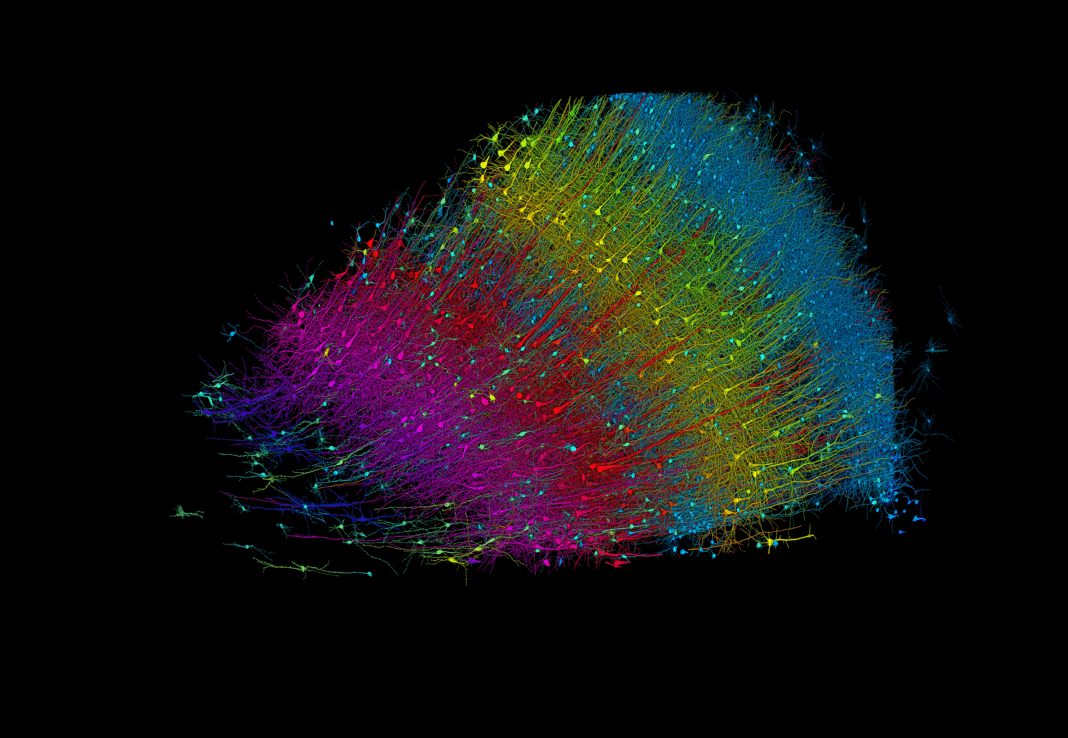

Τη μεγαλύτερη μέχρι σήμερα τρισδιάστατη ανακατασκευή τμήματος του ανθρώπινου εγκεφάλου που δείχνει με μεγάλη λεπτομέρεια κάθε κύτταρο και πλέγμα των νευρωνικών συνδέσεων, δημιούργησαν ερευνητές του Πανεπιστημίου του Χάρβαρντ και της Google Research.

Η ανακατασκευή αφορά ένα κυβικό χιλιοστό εγκεφαλικού ιστού από τον κροταφικό φλοιό, που ωστόσο περιέχει περίπου 57.000 κύτταρα, 230 χιλιοστά αιμοφόρων αγγείων και σχεδόν 150 εκατομμύρια συνάψεις. Το δείγμα ελήφθη από έναν ασθενή με επιληψία, ο οποίος υποβλήθηκε σε χειρουργική επέμβαση.

Χρησιμοποιώντας τα δεδομένα, οι συγγραφείς ανακάλυψαν προηγουμένως υποτιμημένες πτυχές του κροταφικού φλοιού, μεταξύ των οποίων μεγάλο αριθμό νευρογλοιακών κυττάρων πάνω από τους νευρώνες, αλλά και ένα σπάνιο, αλλά ισχυρό σύνολο αξόνων που συνδέονται με έως και 50 συνάψεις. Η χαρτογράφηση θα ανοίξει το δρόμο προς νέες αγνώσεις για τη λειτουργία και τις ασθένειες του εγκεφάλου για τις οποίες οι επιστήμονες γνωρίζουν ακόμη πολύ λίγα.